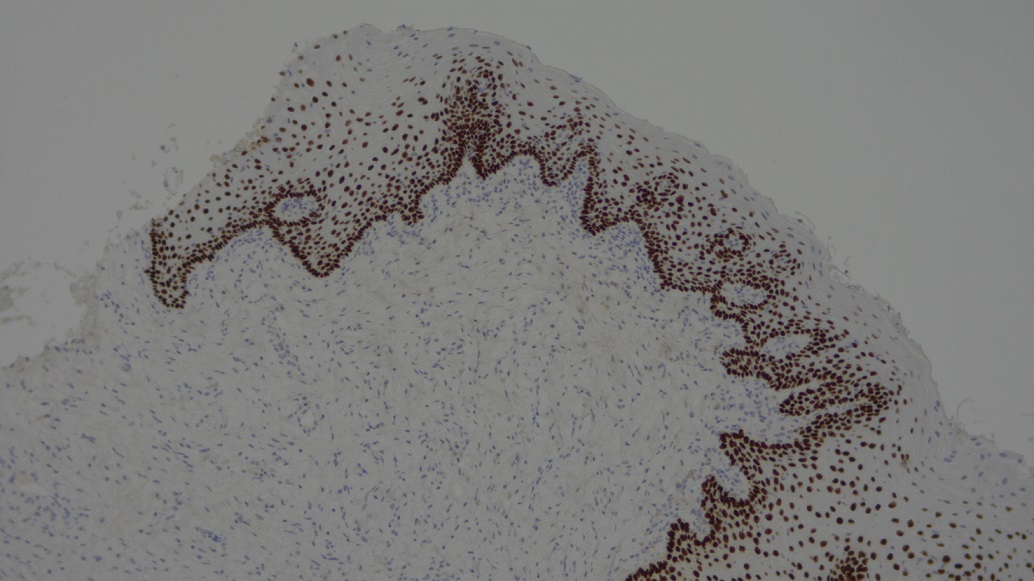

Microscópica Segundo Lugar- Expresión de la proteína p63-Esteban Gordón